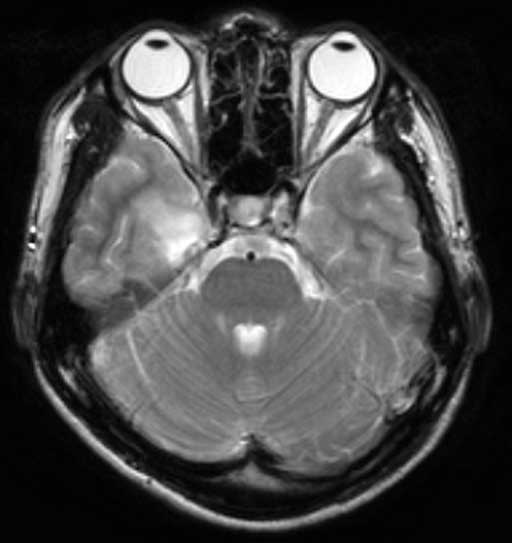

No.54症例2:28歳、男性

平成18年12月中旬に突然頭痛が出現した.平成19年1月に頭痛の精査目的で近医にてMRIを撮像したところ、MRIで右側頭葉に嚢胞性病変を指摘され、当院脳神経外科に紹介受診となった.

• 図2a T2強調横断像

• 図2b T2強調横断像